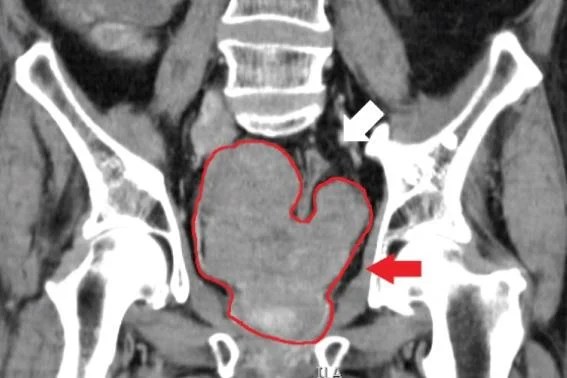

CT scan of prostate cancer. Photo by Mads Ryø Jochumsen/Wikimedia Commons